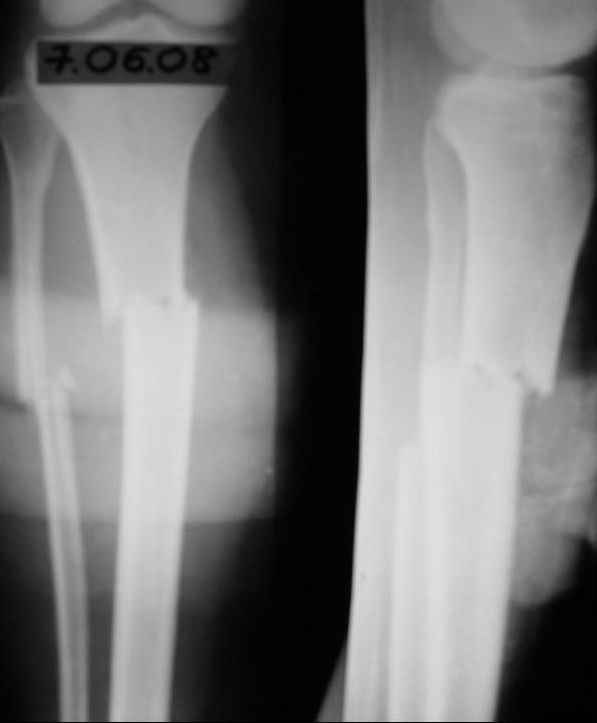

Имя     : 23.03.09.JPG

Тип     : image/jpeg

Размер  : 13381 байтов

Url     : http://weborto.net:8080/pipermail/ortho/attachments/20090417/b6bc8f23/attachment-0007.jpeg

себе опробовала все препараты костной регенерации. В марте удален один из фиксирующих

винтов. На сегодняшний день идет 11 мес. после травмы. Решается вопрос о инвалидности. Буду

благодарен за предложения по дальнейшему ведению больной. Операция?